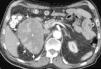

Aldosteronismo primario senil asociado a carcinoma suprarrenal funcionante

Senile primary aldosteronism associated with adrenal carcinoma